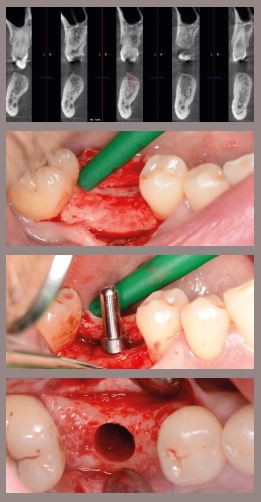

IMMEDIATE IMPLANT PLACEMENT STRATEGIES

- The biologic envelop of extraction site

- Socket type classifications

- CBCT analysis for predictable immediate approach

- Atraumatic extraction techniques

- Timing ( immediate, delayed I.-II., late)

- The predictable 3D implant position

- Implant design for immediate placement

- Immediate loading or temporisation ?

- The role of prosthetic seal

- Surgical Veneer Graft

- Other grafting and membrane considerations

HANDS-ON:

1. Implant placement into various extraction sockets on high-quality bone

model

2. Grafting techniques for socket repair on pig jaw / model